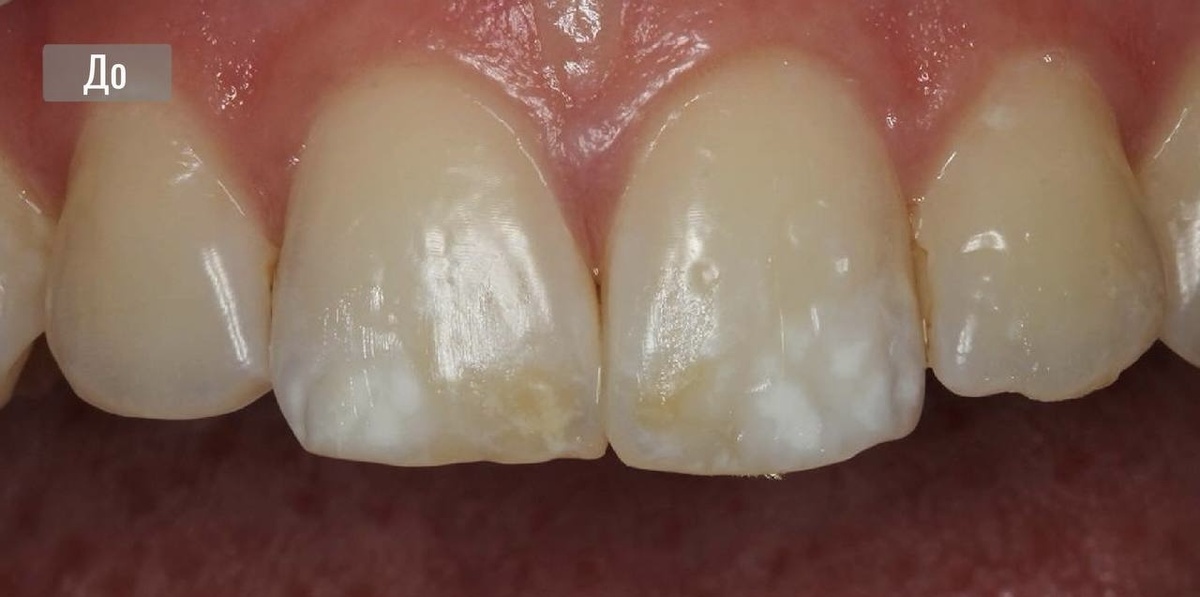

Лечение с помощью ICON, а также микрообразии Opalustre

В данном клиническом случае, представлена эстетическая проблема в области фронтальных зубов, с которой обратилась пациентка 20 лет.

На верхних зубах у пациентки - гипоплазия

Это одно из заболеваний эмали зуба, которое сопровождается изменением цвета, истончением и изменением рельефа тканей.

Гипоплазия не является кариозным поражением, но факторов появления таких пятен множество - от внутриутробных (токсикоз, нарушение обменов веществ в организме матери при беременности, прием антибиотиков) до проникновения инфекции из воспалительного очага молочного зуба в зачаток постоянного.

Многие из врачей, для этой пациентки, предлагали достаточно радикальные методы избавления от таких пятен. Например, закрыть всё композитными реставрациями или винирами.

Но мы все-таки решили применить малоинвазивный подход - сочетанную методику, при которой не требуется препарирование зуба.

С помощью микрообразии снимается поверхностный слой эмали на уровне микрон, а далее он восстанавливается инфильтратом системы ICON.